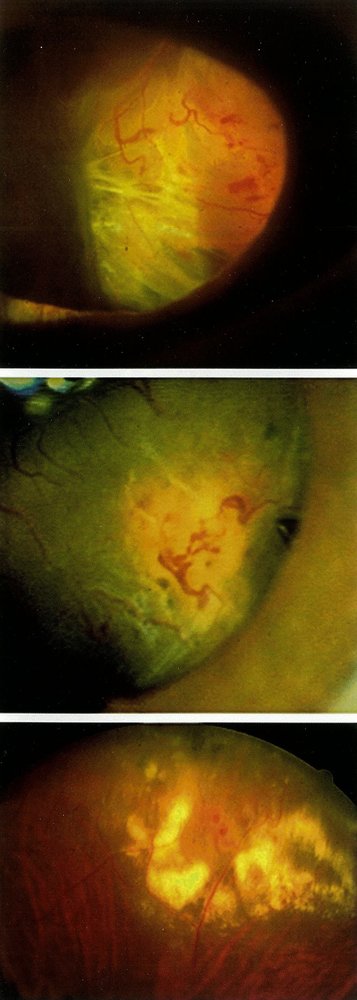

Coats disease (exudative retinopathy)

• Definition: a vascular disease of the retina characterized by retinal telangiectasia, subretinal exudate, and retinal detachment

• Epidemiology

• Incidence: ∼ 1:100,000

• Peak incidence: 5–9 years of age

• Predominantly affects boys

• Clinical features

• Almost always unilateral

• Gradual loss of vision

• Secondary strabismus

• Leukocoria

• Diagnostics

• Ophthalmoscopy: findings include telangiectasias, aneurysms, hard exudates, and retinal detachment

• Fluorescein angiography

• Differential diagnosis: See β€œDifferential diagnosis of leukocoria.”

• Treatment

• Monitoring of mild cases with minimal vascular changes

• Sclerotherapy

• Indications: moderate alterations of peripheral retinal vessels

• Procedures: laser therapy or cryotherapy

• Retinal surgery or enucleation

• Indications: severe cases with retinal detachment and/or painful blindness

• Last resort

• See β€œManagement of retinal detachment.”

• Complications: retinal hemorrhage and/or detachment, blindness